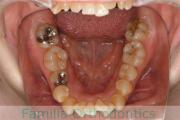

No.22V-212

- 主な症状:

- 叢生

- その他の症状:

- 側方偏位

- 年齢:

- 36歳

- 性別:

- 女性

- 抜歯部位

- 上:

- 88

- 下:

- 8558

- 主な使用装置:

- FEA

- 治療にかかった費用:

- 88万円

見た目を綺麗にしたいとうことで来院されました。重度の叢生(でこぼこ、凹凸、ガタガタ)のため、上下左右から小臼歯を抜歯して、マルチブラケット法を行いました。3年弱、30回程度の通院が必要でした。

本ケースのように叢生が強いと、後戻りのリスクが高いと考えられます。

- ≫治療前

-

上顎

下顎

前歯の関係など

右側

正面

左側